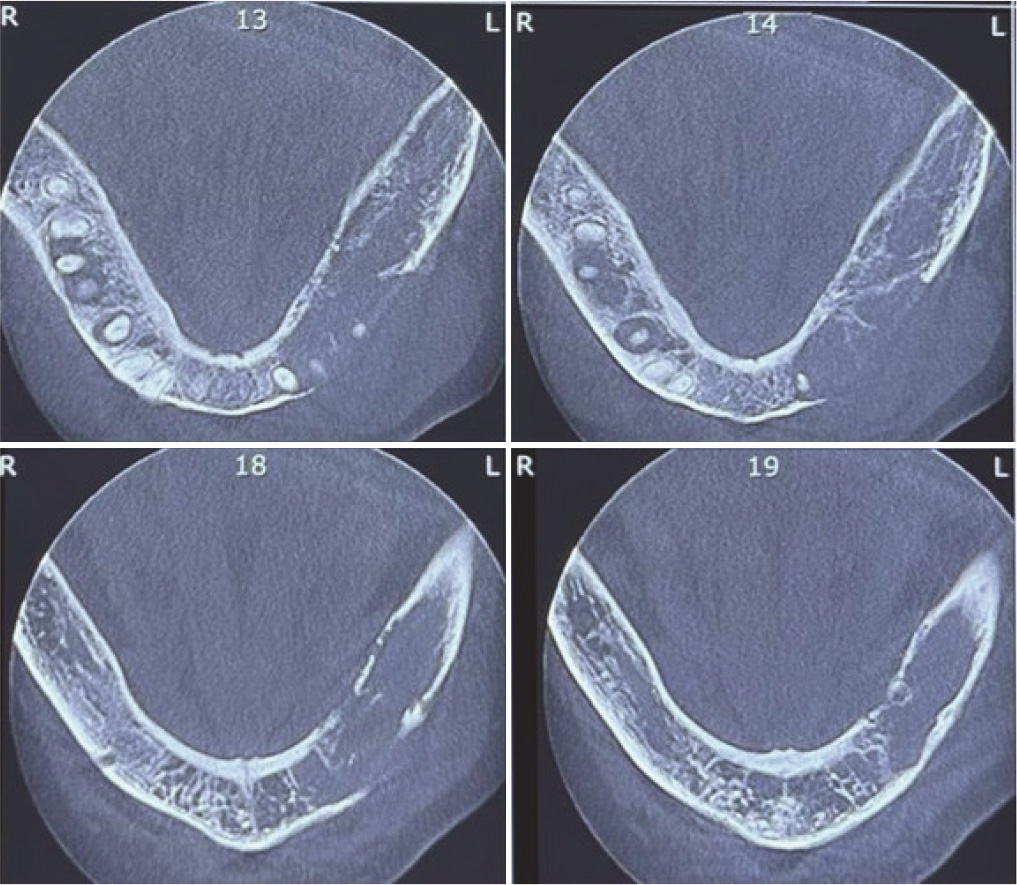

A 57-year-old woman with a chief complaint of left lo-were face swelling was referred to a private dental clinic (Qom, Iran) in October 2023. The intraoral examination revealed mild buccal and lingual expansion from the left lateral incisor extending to the second molar without any mucosal erosion or ulcer. There was no cervical lymphadenopathy (Figure 1a-b). Cone beam computed tomography (CBCT) showed a multilocular radiolucency from tooth 32 to 37 with right angle septa and cortical destruction. The extension of the lesion was more than its expansion (Figure 2). She had a history of right breast cancer in 2017 with a microscopic diagnosis of invasive ductal carcinoma, solid type, stage IIIc. She had undergone a wide surgical excision and chemo-radiotherapy. She took bisphosphonates and was under follow-up. Due to past medical history and radiographic features, a provisional diagnosis of odontogenic myxoma, metastatic cancer, and leukemia/lymphoma was made, and an incisional biopsy was performed under local anesthesia. Histopathologic examination showed a malignant neoplasm composed of sheets of small round cells with hyperchromatic nuclei and mitosis. Considering the medical history and microscopic features, an overall diagnosis of a small round cell tumor was rendered, and immunohistochemical (IHC) staining for cytokeratin (CK), leukocyte common antigen (LCA), CD-99, GATA3, estrogen (ER), progesterone (PR), and HER-2 was recommended. IHC was only positive for GATA3 and CK (Figure 3b, Figure 4a). Findings were consistent with metastatic carcinoma of breast origin. In whole-body scans and CT with and without contrast, no focus of involvement was seen except for the left mandibular area. Tumor markers such as CA15-3 (40.2u/ mL) were higher than the normal range (up to 31.3), but CEA (1.05ng/mL) and CA125 (12.2u/mL) were in the standard limits. Due to bone (mandible) metastasis, the patient was placed in stage IV. She was referred to an oncologist to complete the treatment. She has undergone two courses of chemotherapy and one course of radiotherapy, and after 13 months (November, 2024), the general condition of the patient was acceptable.

Figure 2. Axial views of the cone beam computed tomography reveal tumor extension and cortical destruction